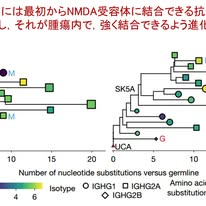

・もともと存在していた抗体が腫瘍内で進化して病的抗体になる―NMDA受容体脳炎の新しい理解

***岐阜大学医学部下畑先生の2026年3月30日のFB投稿です***

米国Cold Spring Harbor Laboratoryからの研究で,NMDA受容体脳炎という傍腫瘍性神経症候群を手がかりに,「自己抗体はどのように生まれるのか」という根本的な問いに対して1つの答えを提示したものです.さらに本研究は臨床的アプローチにおいても影響を与える重要な示唆を含んでいます.

米国Cold Spring Harbor Laboratoryからの研究で,NMDA受容体脳炎という傍腫瘍性神経症候群を手がかりに,「自己抗体はどのように生まれるのか」という根本的な問いに対して1つの答えを提示したものです.さらに本研究は臨床的アプローチにおいても影響を与える重要な示唆を含んでいます.

まず研究モデルについてです.本疾患は卵巣奇形腫と関連して説明されることが多く,腫瘍内の神経組織が抗原となって抗体が産生されると考えられてきました.しかし奇形腫では抗原が多彩であり,どの要素が本質なのかを明らかにすることが困難でした.このため,本研究では神経とは無関係な腫瘍を用い,そこに神経抗原という単一の要素を追加して影響を調べるという戦略がとられました.具体的には,トリプルネガティブ乳がん細胞にNMDA受容体(GluN1,GluN2B)を誘導発現させる動物モデルを構築し,「神経抗原が腫瘍に出現するだけで自己免疫が成立するのか?」を直接検証しています.

まず研究はヒト腫瘍の解析により,トリプルネガティブ乳がんの一部の細胞がNMDA受容体を発現していることを示します.本来中枢神経で機能する分子が,腫瘍において異所性に発現しうることを示しています.つぎに上述したマウス腫瘍にNMDA受容体を人工的に発現させる動物モデルを検討しました.そしてこのモデルでは,腫瘍にNMDA受容体を発現させると短期間でNMDA受容体抗体が産生されること,そしてそのピークに一致して腫瘍の縮小が認められることを示しました.腫瘍内にはB細胞やT細胞が集積し,三次リンパ構造の形成も確認されており,局所で強い適応免疫応答が成立していることが示されました.つまりこの抗体は抗腫瘍効果を持つわけです.

そして本研究の核心は,この抗体の起源を単一細胞レベルで追跡した点にあります.図1では,腫瘍内B細胞の抗体遺伝子が系統樹として示されており,抗体が変異を重ねながら進化していく様子が描かれています.ここで最も重要なのは,最も根元(図の左側)に位置する変異のない抗体(germline抗体)の段階で,すでにNMDA受容体に結合できる点です.この「germline抗体」とは,まだ変異を受けていない,いわば生まれたままの抗体のことです.通常,抗体は抗原に出会うことで変異を重ね,より強く結合できるように進化していきますが,本研究ではこの出発点の段階ですでにNMDA受容体に弱いながらも結合できることが示されました.言い換えれば,私たちの体には最初から「自己に反応できる抗体」が存在していることを意味します.

そして腫瘍内で抗原刺激が持続すると,この抗体が変異を重ねて結合力を高め,最終的に強く反応する病的抗体へと変化していきます.すなわち,自己抗体は新たに生じるのではなく,もともと体に存在する自然抗体が進化したものであることが明確に示されました.この概念は,自己免疫疾患の理解そのものを大きく変えるということでNature誌に掲載されたのだと思います.

次に重要なのが,この抗体が中枢神経に到達した場合にどのような影響を及ぼすかです.図2では,本研究で同定されたNMDA受容体抗体(SK3D)をマウスの脳内に直接投与した実験において,抗体が海馬に分布していることが免疫染色で示されています.すなわち,抗体が脳内に存在すれば標的に結合し得ることが確認されています(血液脳関門をこの抗体が通過するかは調べていません).さらに図3では,受容体活性を増強する抗体(SK3D)を脳内に投与したマウスにおいて,短時間のうちにけいれん様発作が繰り返し出現する様子が示されています.対照抗体(mGO53)ではこのような変化は認められません.この結果は,抗体そのものが神経回路の興奮性を変化させ,臨床症状を直接引き起こすことを明確に示しています.つまり同じ抗体が腫瘍に対しては抑制的に働く一方で,神経に対しては病原性を持つという二面性を持っているということです.この事実は臨床的に重要と思われます.

本研究の意義を考えてみたいと思います.まず診断の観点では,「抗体が検出された場合には,その背後に抗原提示を行う腫瘍が存在する可能性が高い」ということです.すなわち,NMDA受容体抗体を認めた場合,どこかで抗原刺激があるはずで,やはり徹底した腫瘍検索が求められるということです.次に治療の観点では,免疫抑制のバランスという課題が浮かび上がります.自己免疫症状を抑えるために免疫を強く抑制すれば,抗腫瘍免疫も同時に低下する可能性があります.よって強力な免疫抑制療法を行う場合には腫瘍への対策がより求められます.

さらに免疫チェックポイント阻害薬(ICI)による自己免疫性の副作用の理解にもつながります.つまり私たちの体にもともと存在する弱い自己反応性の抗体が,ICIによる免疫の活性化によって増幅され,強く反応する抗体へと変化することで病気が生じる可能性を示しています.これは私たちのチームでもしばしば議論していましたが,ICIによる副作用は「新しく異常な抗体が生まれる」のではなく,「もともと存在していた抗体が強くなりすぎる」と理解することができるのだと思います.

加えて,抗体の機能的多様性という視点も重要です.詳細は省きますが,本研究では,受容体の活性を増強する抗体と抑制する抗体が存在することが示されており,将来的には抗体の有無ではなく,機能に基づいた病態分類や治療選択が求められる可能性もあります.

結論として本研究は,腫瘍における神経抗原の異所性発現が,もともと存在するgermline抗体を活性化し,親和性が増した病的自己抗体を生み出すこと,そしてその抗体が腫瘍抑制と神経障害というトレードオフの関係にあることを明らかにした点できわめて重要な研究だと思いました.

Kleeman SO, et al. Ectopic NMDAR expression in cancer unmasks germline-encoded autoimmunity. Nature. 2026 Mar 25. doi: 10.1038/s41586-026-10278-0. PMID: 41882353.